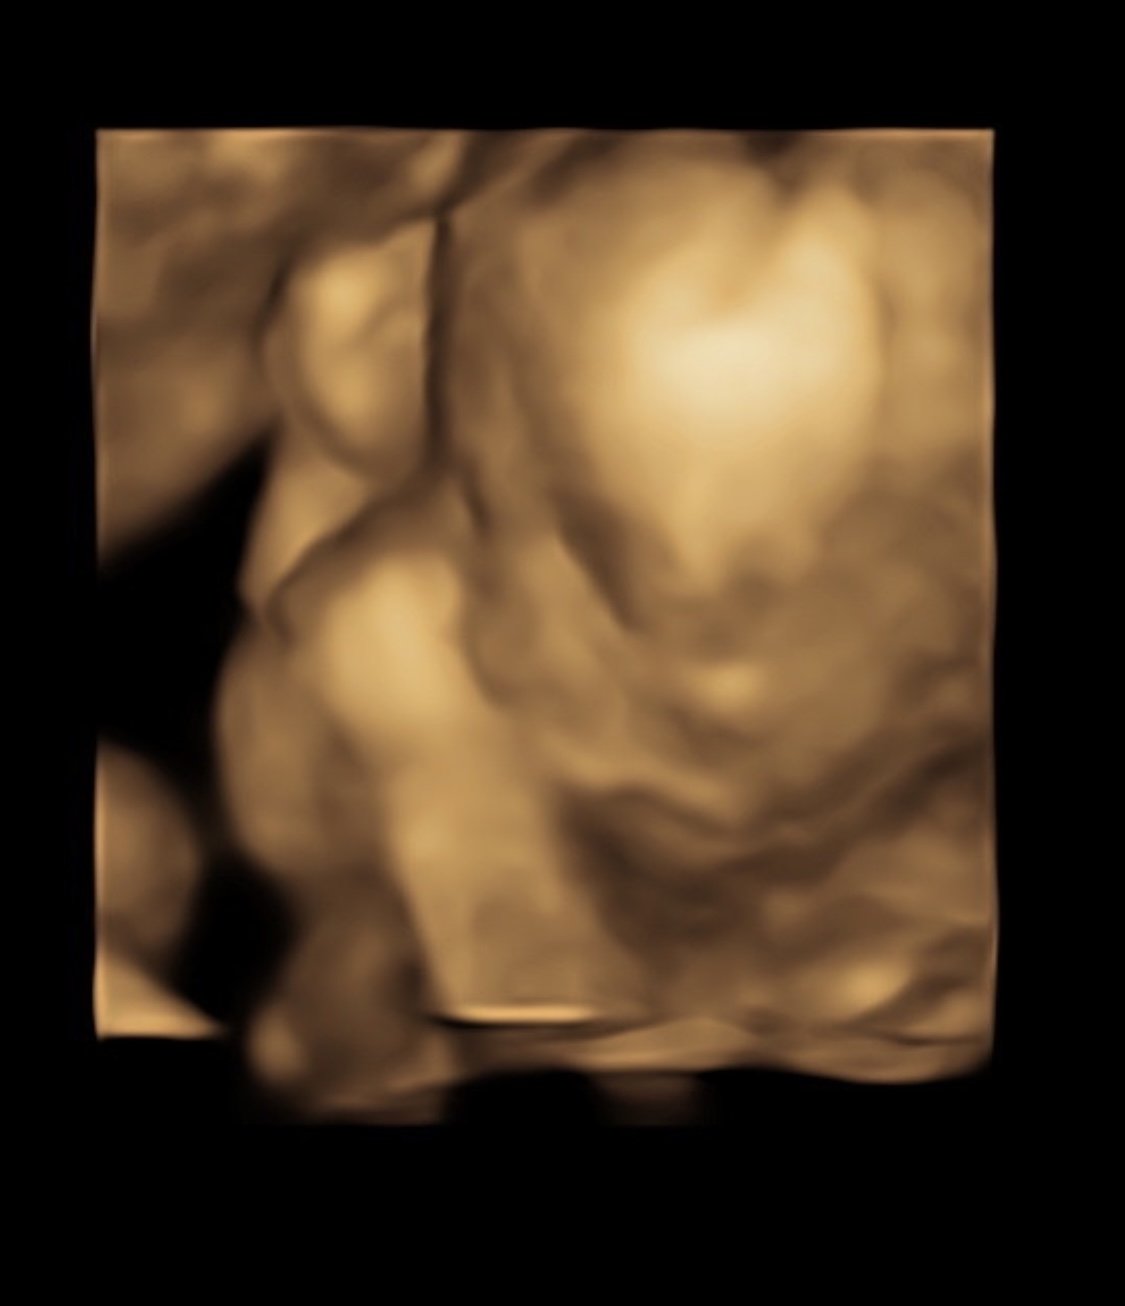

Bonus of a second scan in 3 days = I got 3D pics this time! Always a little creepy but this one is my favorite.

We had our follow up scan today to get the remaining pictures of baby girl's heart - all looks great, thank goodness! She's sucking her thumb here. She was still very active OR curled up in a ball and didn't want to move. Stubborn like her mama.